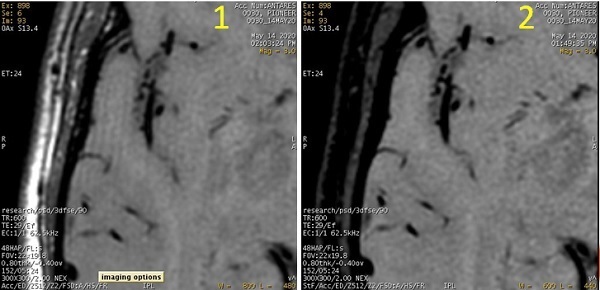

Figure 1. Carotid vessel wall image comparison

Table 1. Image legend

RowsLeft columnMiddle columnRight column

1 = 3DTOF

2 = Cube

3 = Cube with MSDE (Vessel T1)

Right CCA bifurcation Sagittal reformatLeft CCA bifurcation

Sagittal reformat

CCA bifurcation

Axial reformat